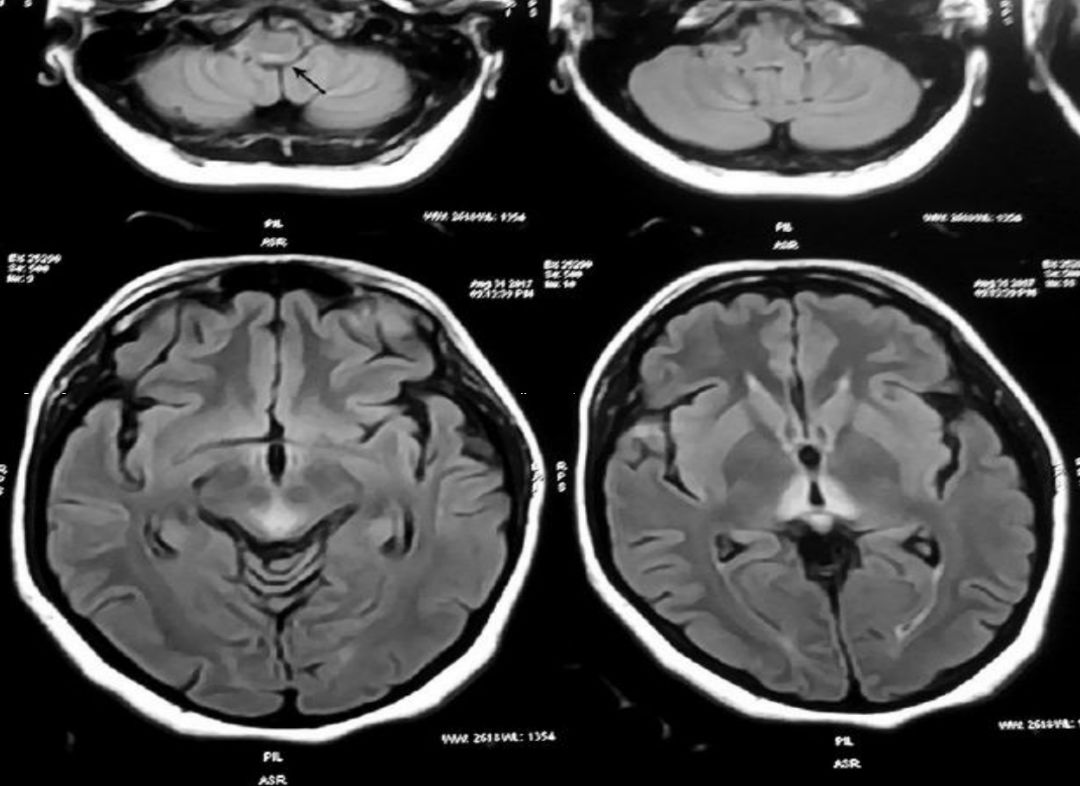

男性18岁,发热、恶心、呕吐3天。(补充:自行口服甲硝唑1.2g/d 后出现共济失调、眩晕。)

答案: 甲硝唑相关脑病(Metronidazole-induced encephalopathy MIE)。

本周一的晨读病例都是良心病例,难度程度均不高。特征性影像表现剑指甲硝唑和山豆根。甲硝唑的神经毒性主要包括前庭小脑系统损害、自主神经损害、视神经损害、周围神经损害及癫痫发作等。甲硝唑引起的CNS损害多具有可逆性,及时停药后,临床症状可短期内改善。MIE的MRI改变:典型病变区域在小脑齿状核、中脑、脑桥被盖、延髓背侧及胼胝体压部,通常双侧对称受累。小脑齿状核和中脑下丘对称性病灶被认为是MIE的特征性表现。MIE鉴别诊断:中枢神经系统脱髓鞘疾病及其他代谢性和中毒性脑病。其中,Wernicke脑病最需与MIE鉴别。WE特征MRI表现:第三、四脑室旁、导水管周围、乳头体、四叠体、丘脑对称性病灶。